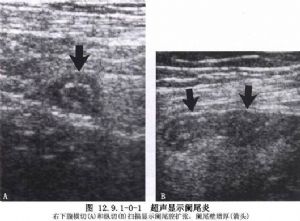

急性闌尾炎是外科很常見的一種疾病。闌尾切除術是最爲普通、常行的手術之一,但有時很困難,因此,對每一例手術均須認真對待。急性闌尾炎是小兒最常見的急腹症。由於小兒闌尾壁薄,穿孔率高;腹腔對感染的侷限能力差,一旦穿孔常造成瀰漫性腹膜炎;同時小兒又多因診斷延誤而未能早期治療,所以臨牀所見小兒闌尾炎病情較重。因此,小兒闌尾炎一旦確診,應立即手術治療(圖12.9.1-0-1,12.9.1-0

-2)。